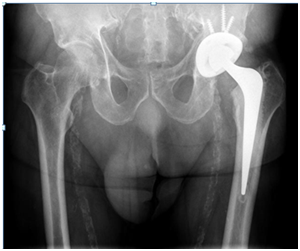

Two stage treatments consisted in an initial surgery through a posterior approach, debridement of inflammatory tissues, neck osteotomy and acetabular reaming adding a temporal non-articulated antibiotic impregnated cement spacer for the resected femoral head. 6 weeks after surgery when intravenous antibiotic treatment was completed and laboratory inflammatory parameters were controlled, a second stage surgery was planified: Conversion to a hybrid arthroplasty for the first case and a non cemented total hip arthroplasty for the second case (Figure 1) (Figure 2).

Figure 1: 60 year old diabetic male patient. A and B Plain X rays showing the narrowing of the hip joint, consequent to a psoas absess. C, D are MRI images showing the acetabular edema and sinovytis associated to psoas edema. E and F postoperative arthroplasty x-ray. Differed anatomy showed chronic inflammation compatible with osteomielitis but no germs were isolated in the cultures. Harris Hip score was 94 at 2 year follow up, infection markers controlled and no complications were reported.